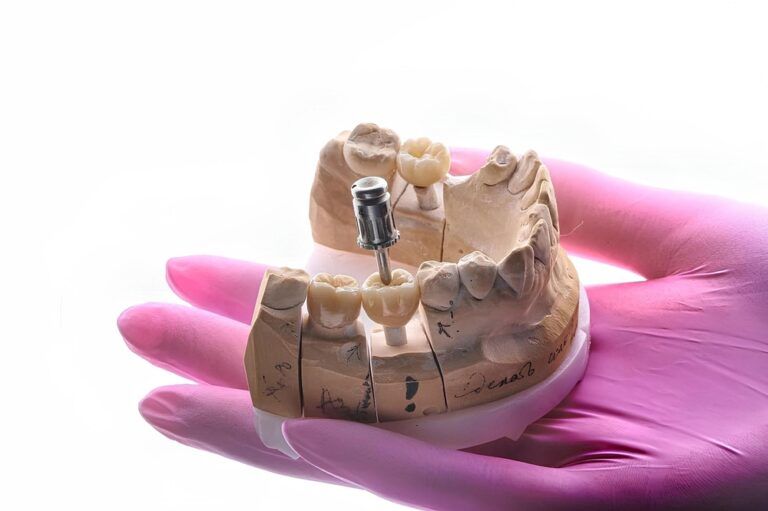

All-on-4 Restorations: How Precision Lab Work Makes the Difference

For patients in Chicago seeking full-arch tooth replacement, All-On-4 implants have revolutionized restorative dentistry. These restorations utilize four strategically placed implants to support an entire arch of teeth, offering a stable, long-lasting solution compared to traditional dentures. The precision of each restoration